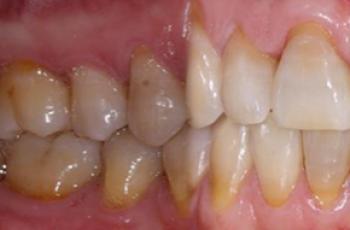

Tratamiento no quirúrgico de la periimplantitis. A propósito de un caso... Cirugía periodontal y periimplantaria | UIC Tratamiento no quirúrgico de la periimplantitis. A propósito de un caso... Se presenta el caso de una paciente de 58 años de edad, sin antecedentes médicos de interés y no fumadora. El motivo... Etiología, diagnóstico y tratamiento de la periimplantitis: Caso... Tto. Periimplantario | UV Etiología, diagnóstico y tratamiento de la periimplantitis: Caso... Presentamos nuevo caso clínico realizado por los doctores Manuel Rodríguez Aranda, Francisco... Efectividad del Tratamiento en Periodontitis Agresiva Tto. Periodontal | UIC Efectividad del Tratamiento en Periodontitis Agresiva El mantenimiento de la dentición natural en estado de salud ha sido un objetivo importante en... Injerto gingival libre alrededor de implantes dentales. A propósito de un... Cirugía periodontal y periimplantaria | UIC Injerto gingival libre alrededor de implantes dentales. A propósito de un... La cirugía mucogingival reconstructiva alrededor de implantes corrige los defectos de la... Terapia mucogingival en implantes: corrección de las secuelas mucosas de... Cirugía periodontal y periimplantaria | UV Terapia mucogingival en implantes: corrección de las secuelas mucosas de... El caso que se presenta a continuación muestra una resolución impecable de un defecto mucogingival... Importancia del mantenimiento en la evolución de un paciente con... Mantenimiento | UV Importancia del mantenimiento en la evolución de un paciente con... La periodontitis agresiva se define como una enfermedad de rápida progresión en la destrucción... Tratamiento de Recesiones Gingivales Clase III de Miller mediante técnica... Cirugía periodontal y periimplantaria | UIC Tratamiento de Recesiones Gingivales Clase III de Miller mediante técnica... El caso clínico que presentamos a continuación es el de una paciente que acude a la consulta... Tratamiento de un paciente con periodontitis crónica moderada generalizada Tto. Periodontal | UIC Tratamiento de un paciente con periodontitis crónica moderada generalizada El caso clínico que se presenta a continuación, muestra el tratamiento de una paciente...